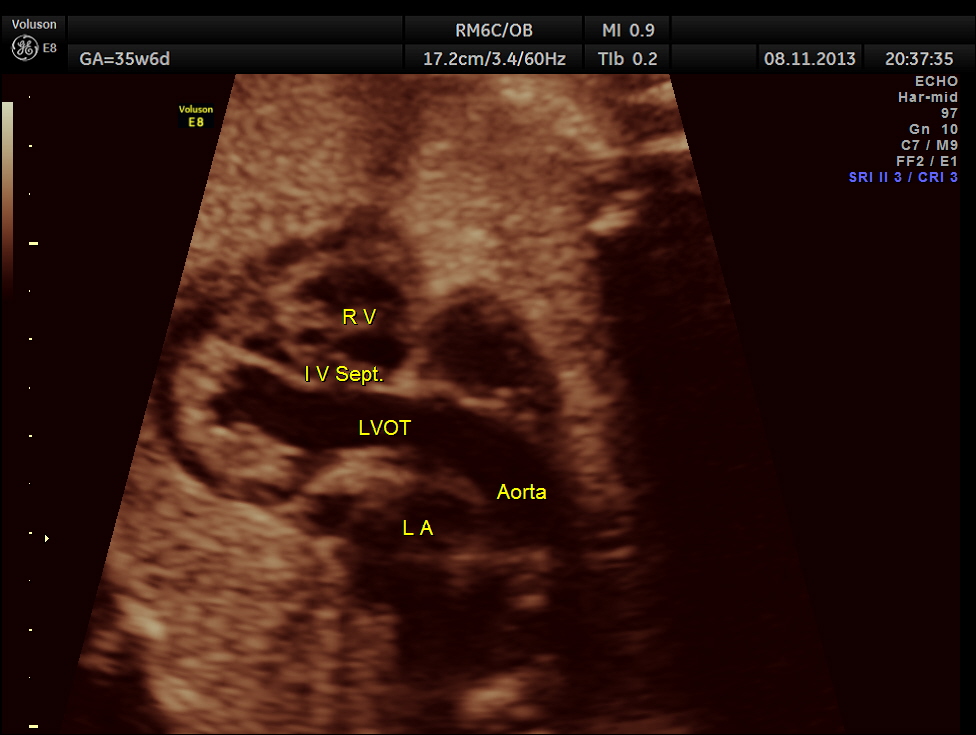

The scan was repeated at 36 weeks of gestation.